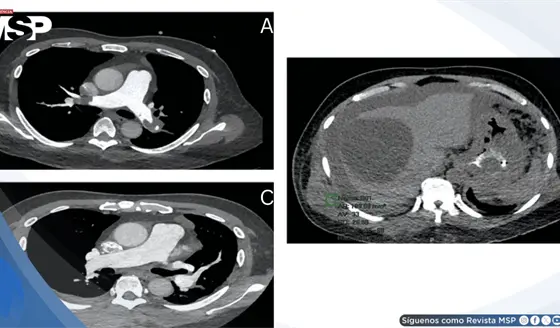

Embolia pulmonar en silla de montar asociada a fármaco en paciente con enfermedad renal y cáncer gástrico